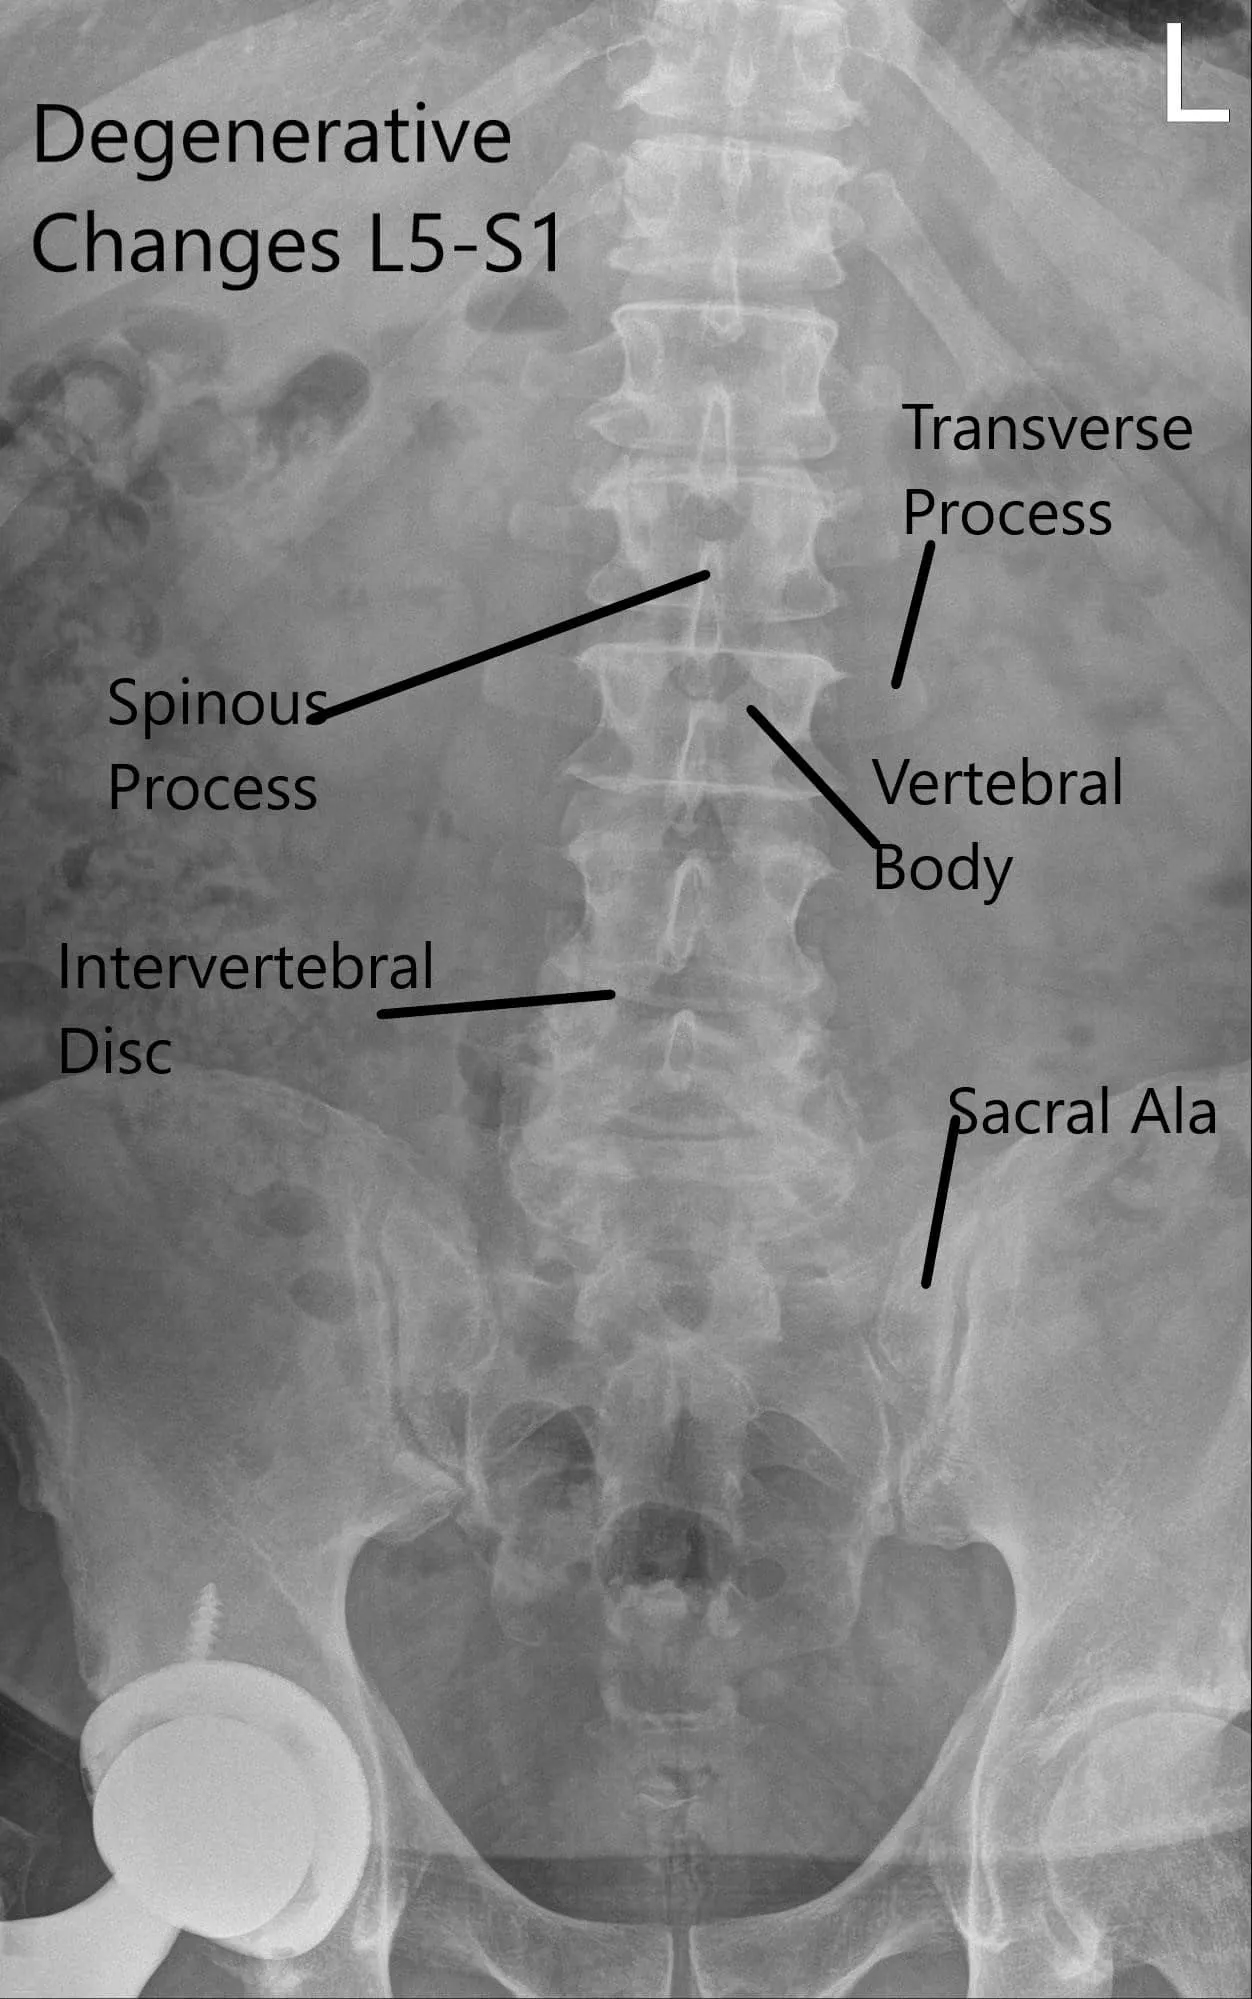

X-ray of the lumbar spine was reviewed with the patient. The X-ray revealed severe degenerative changes at L5-S1 and 5 mm anterolisthesis at L4-5.

Preoperative X-ray LS spine in AP and Lateral Views.